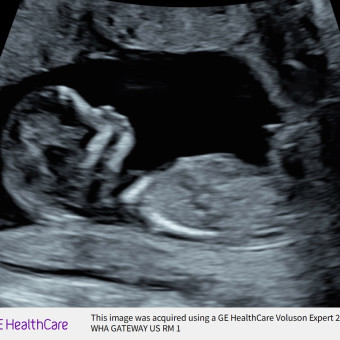

Gabriel

Jimmy Cisterna & Cristina Hernandez

July 8, 2026